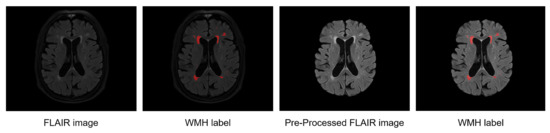

2.5.1. Annotated Labeling with Radiologists

2.5.2. Preprocessing